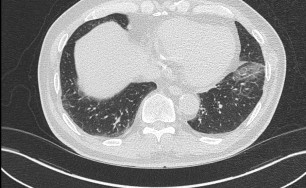

측농증

호흡기 질환만 연구, 숨케어한의원